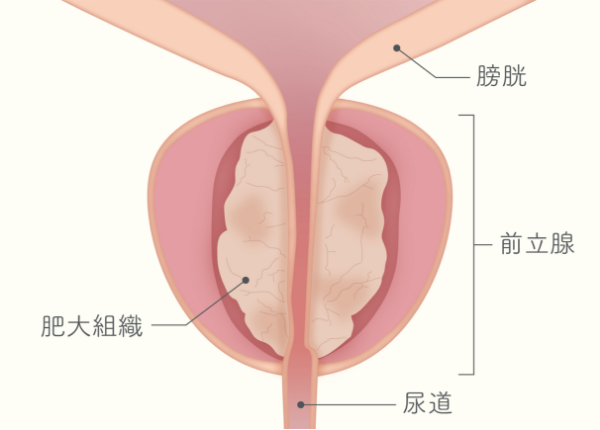

前立腺肥大症とは

前立腺肥大症は加齢とともに増加し、80歳以上では80%を超えると言われています。

肥大した前立腺が尿道を圧迫すると、尿の出が悪くなったり、日中や夜間の排尿回数が増えるなどの症状が出現し、重度の前立腺肥大症では、自力で排尿がまったくできなくなってしまう尿閉と呼ばれる状態になることもあります。